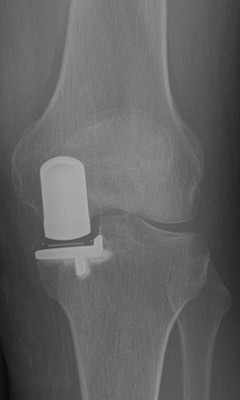

Das Kniegelenk besteht aus drei Gelenkkompartimenten: einem inneren, zentralen und äußeren Kompartiment. Die Kniescheibe bildet ein Widerlager und gleitet über den Oberschenkelknochen. Prinzipiell ist ein isolierter oder kombinierter Verschleiß vom inneren oder äußeren Gelenkkompartiment sowie auch dem Kniescheibenwiderlager möglich. Erkennt man die Erkrankung früh genug und ist der Leidensdruck entsprechend, so kann man die einzelnen Kompartimente isoliert ersetzen.

Sollte bei Ihnen eine Endoprothese in Frage kommen, wird durch Beurteilung verschiedener Faktoren der Prothesentyp aus dem o.g. Portfolio für Sie ausgesucht.